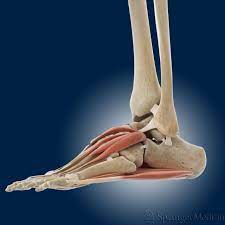

Andere Erkrankungen der Füße entstehen durch Krankheiten die viele Bereiche des Körpers betreffen wie Diabetes mellitus Gicht oder andere Arthritisformen. Die Knochen des Fußskeletts werden durch zahlreiche Bänder zusammengehalten und sind durch Gelenke miteinander verbunden. Alle von diesen Cookies erfassten Informationen werden aggregiert und sind deshalb anonym.

Trochanter Trochanter der Rollhügel su. Jeder Teil des Fußes ob Knochen Muskel Gelenk Sehne oder Band kann betroffen sein. Verschiedene Gelenke Muskeln Sehnen Bänder Nerven und Blutgefäße sorgen dafür dass die Füße zugleich stabil und beweglich sind. Klicken und ziehen um das 3D-Modell auf der Seite. Länger bestehende Schmerzen an der Fußaußenkante sind nicht physiologisch und müssen aufgrund möglicher behandlungsbedürftiger Ursachen ärztlich abgeklärt werden. Die Bruchstelle liegt hier meist an der Basis des zweiten Mittelfußknochens. Trochanter lat Rollhügel s.